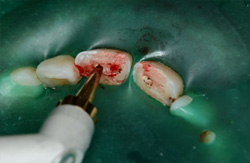

神経の露出した処置を行います。上の部分を少しだけ取って残りの部分を残します。部分的な断髄といいます。根の治療(歯内療法)をするときは必ずラバーダム防湿(緑の膜)をおこないます。感染防止のためラバーダムをしない根の治療はありえません。一番の成功のポイントです。 |